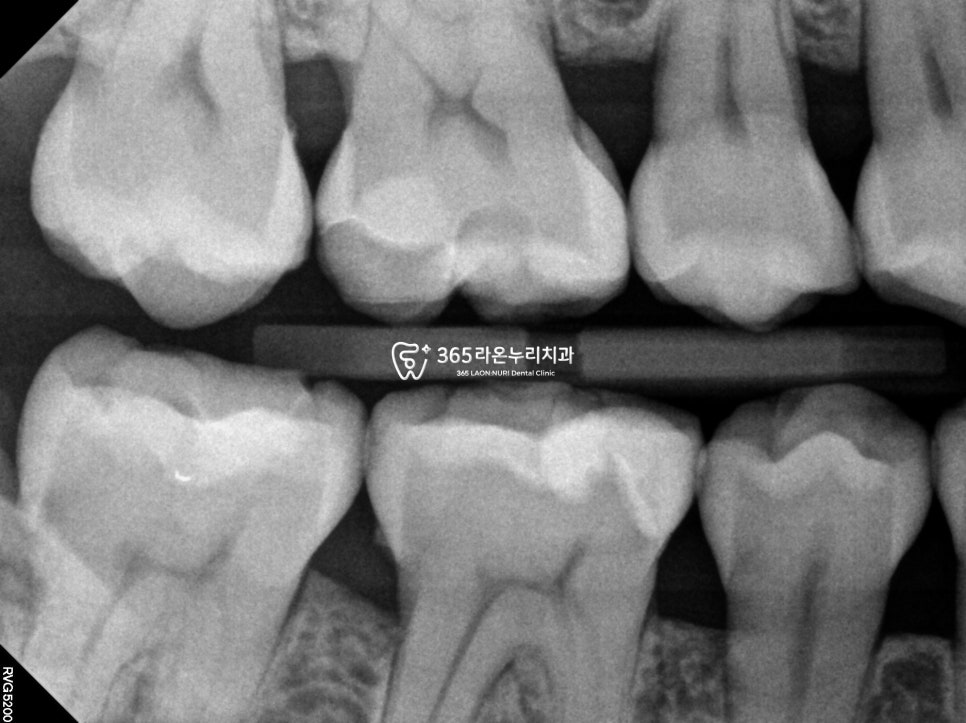

치료 전 우식증이 더 깊게

진행된게 없는지

방사선 사진을 통해

확인을 하게 되는데요.

남아 있는 치아를 보존하면서도

심미성과 기능을 함께 회복할 수 있는

‘원데이 인레이'(oneday inlay)를

이용한 복원을 계획할 수 있는데요.

세마동 치과 에서 보여드리는

이 사례에서는

훼손 부위가 비교적 깊었으나,

구조적으로 유지할 수 있는 부분이 충분해

크라운보다는 inlay가 더 알맞다고

보입니다.

방치할 경우 내부 신경

훼손이 갈 확률이 있었기에,

훼손 범위를 고려해 선택하게 된 것으로

생각됩니다.